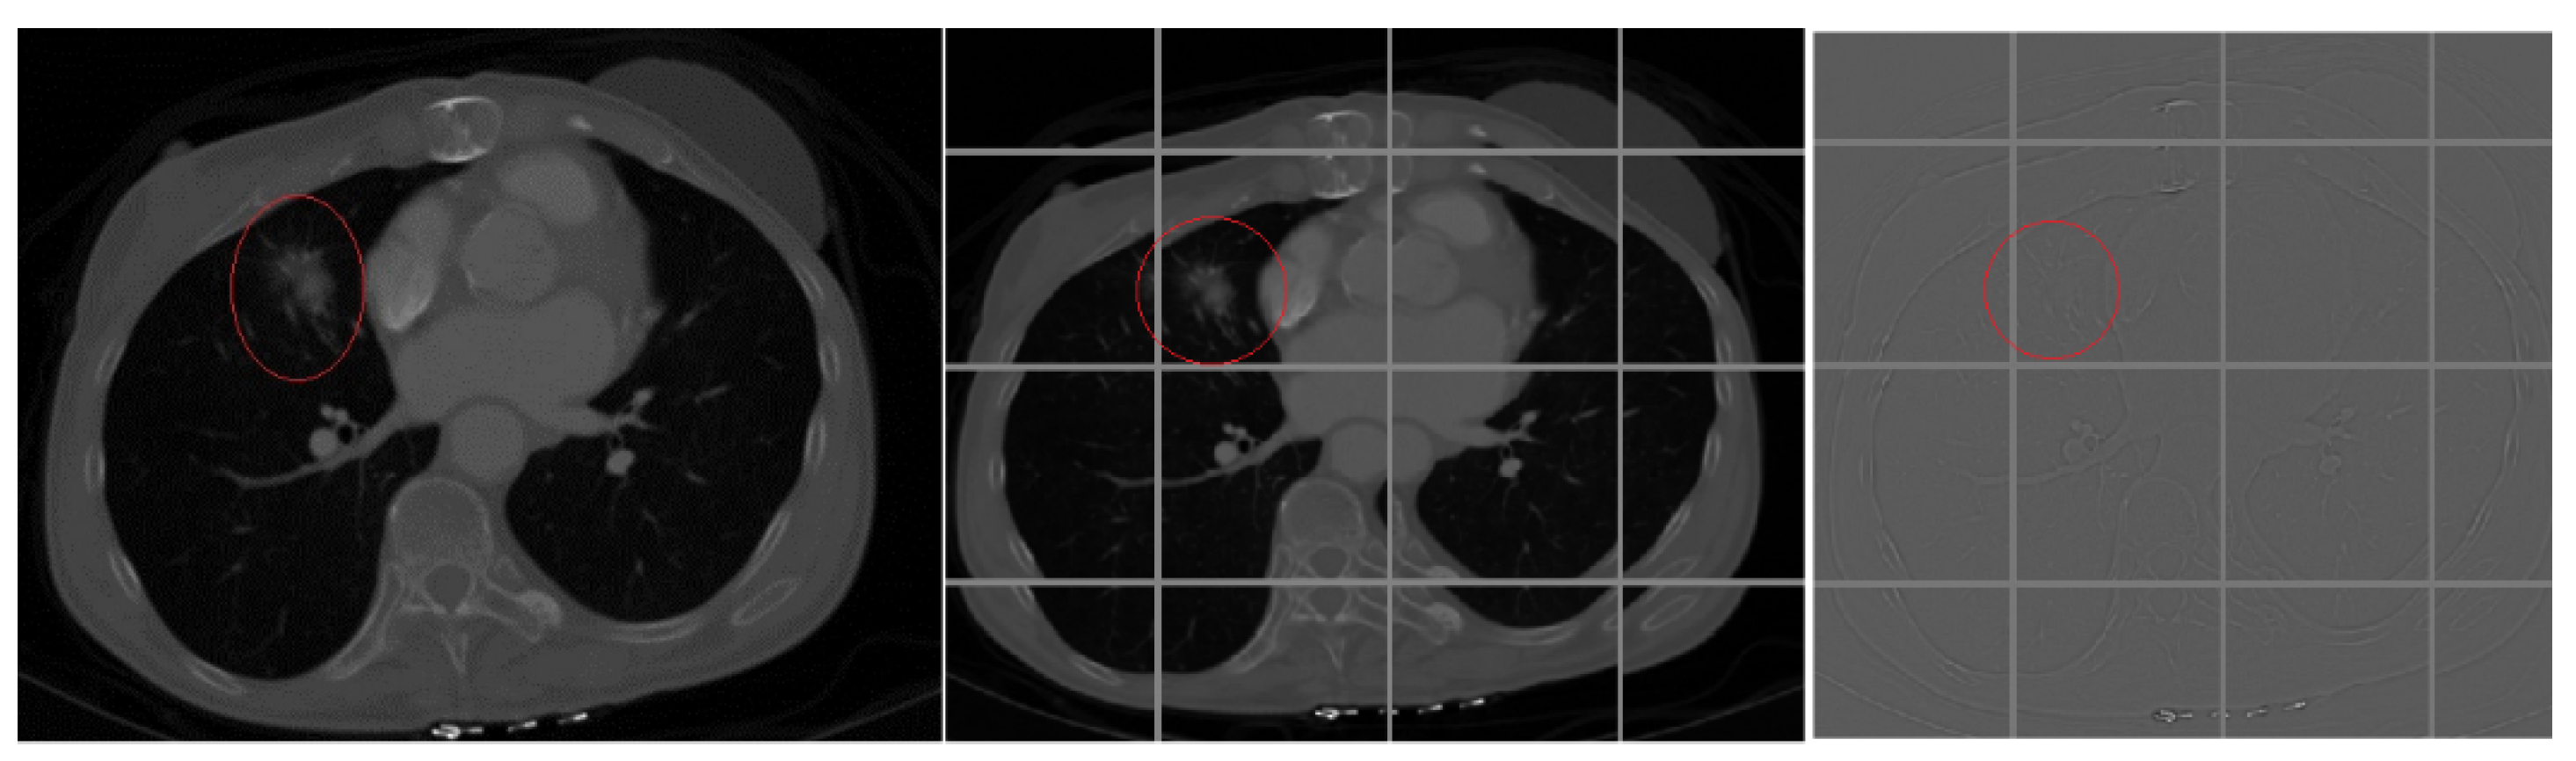

Next, we needed to further group the images in the two piles, where each group represented images from same slice (angle of the chest of the patient). This way, we created 64 groups within each pile, where each group in Pile 1 (cancer pile) had 73 CT images. Each of the 64 groups of Pile 2 (cancer-free pile) had 22 CT images. A sample of different angle (slice) CT images is shown on Figure 2. The middle image is cancer-free (belongs to Pile 2) and the other two are with marked location of the cancer (form Pile 1). Creating the piles of images was done so that we can create positives and negatives to train and test the network, but the groups in each pile were created so that Deep Neural Network would focus on recognizing same slice (angle) images. The groups were created using K-means algorithm to group the image into the appropriate slice group. The reason we used the K-means clustering is because we had CT images that were taken from 16-, 32-, 64-, 128-, 256- and 320-slice CT scanners. We used 64 groups because most of the images we had were 64-sliced. For images obtained from a scanning that made more or fewer than 64 slices, we used the K-means algorithm to put them into the correct group.

Figure 2.

Different angles of CT lung cancer images.

When the DNN is trained, the bias factor can be more precisely calculated and the correlations between the nodes adjusted. What the convolution does to an image is shown in Figure 5.

Figure 5.

Convolution of a CT scan image with kernel filters for edge sharpening filters.

As shown in Figure 5, we further divided the image into smaller parts, where the parts overlap. This way, we could focus on (isolate) a certain part of the image and use that (smaller) image to search for a pattern. In our network, we defined the convolution parameters and the slicing window. Our convolution layer takes input of 128 × 128 × 1 (width × height × color). We used 1 for color (depth) since the image was grayscale. Furthermore, we used Rectified Linear Unit as an activation function, which means that all negative values of activation are replaced with a value of 0. There is a tradeoff here as to how much overlapping there should be. If we increase the overlapping, we make more window images and thus more detailed search. However, by doing so, we slow down the process of learning and classifying, as the window-cutting requires more resources. Since the convolution results in more smaller images from the original one, by using max-pooling, we reduce the size of these images into chunks of data, where we get the most (maximum) of every image. This means that we searched for the cancer by upsizing the image in one layer and downsizing the results in the next by maximizing the bias (similarity) between adjacent kernels of the convolution. In the convolution function, we mainly used sharpening and edge detection filters. The filter in the convolution is a simple matrix that convolutes the image matrix and the result is another image whose edges are sharpened. The resulting image of the convolution filters is the third image in Figure 5.